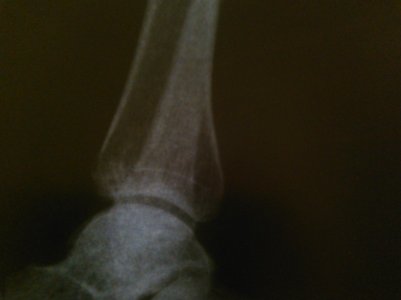

Здравствуйте, мне 39лет. Упала 27ноября2015г. На R- снимке за 27.11.15.и 22.12.15. костных травм, повреждений не выявлено. В лангете проходила 2 недели, 24декабря выписали на работу(на одной ноге прыгала), боль сохранялась в левой стопе, наступать на стопу не могла.

Отдельно прилагаются фото МРТ, КТ, рентгенография.